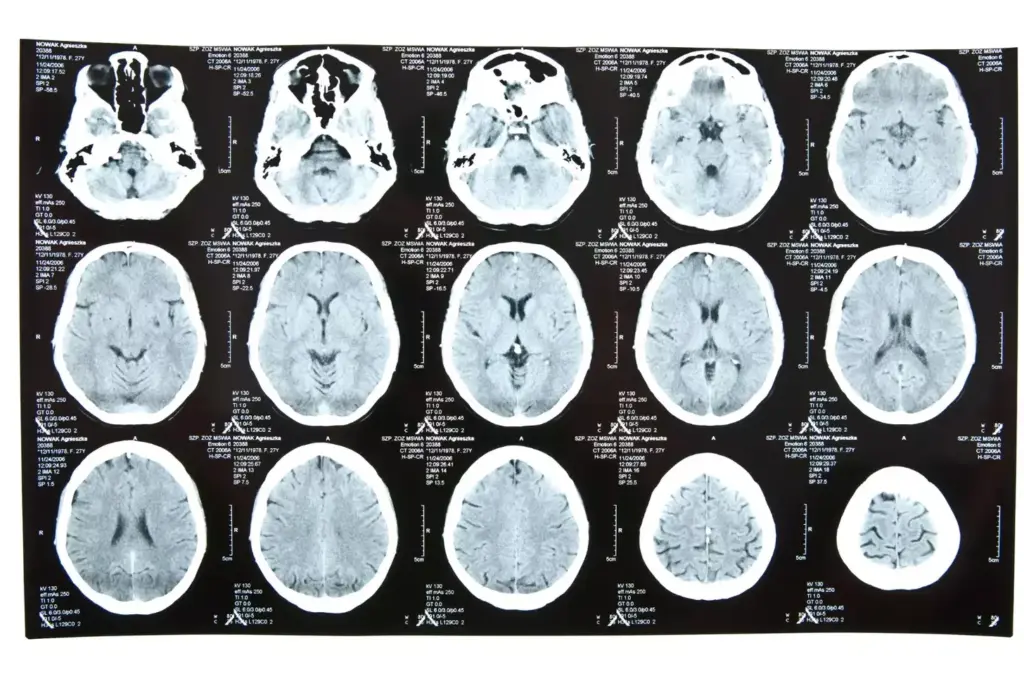

Finding brain cancer early makes a big difference. Early tumors are easier to treat, leading to better chances of survival. New imaging tools like MRI and CT scans help doctors spot tumors better.

Recently, brain cancer treatment has seen big changes. New imaging tools like MRI and PET scans help doctors diagnose and stage tumors more accurately. Surgery has also improved with less invasive methods and better imaging during operations.